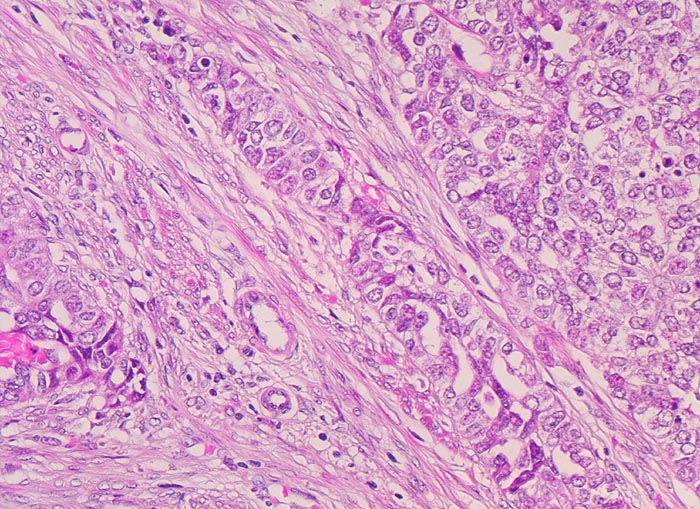

Endometrioide Karzinome bestehen aus tubulären Drüsen, welche von einem mehrreihigen Epithel ausgekleidet werden. Schleim ist meist nicht oder nur apikal in den Zellen vorhanden. Die Ausdehnung der soliden Areale und die zytologischen Atypien bestimmen den Differenzierungsgrad (low-grade versus high-grade). Metaplastisches Plattenepithel findet sich häufig in endometrioiden Karzinomen und hilft bei der Abgrenzung von anderen Subtypen. Das endometrioide Karzinom kann sich innerhalb von Adenomyoseherden im Myometrium entwickeln (> 4482). In diesen Fällen kann die Bestimmung der Infiltrationstiefe erschwert sein.

• Anstelle des Endometriums findet sich in der linken Hälfte des Uteruskavums ein Adenokarzinom bestehend aus architektonisch komplexen Drüsen. Die Drüsen liegen teils dos à dos ohne erkennbares Stroma zwischen zwei Drüsenschläuchen.

• Tumorzellverbände infiltrieren die glatte Muskulatur des Myometriums.

• Tumordrüsen ausgekleidet von mehrreihig angeordneten Tumorzellen mit hyperchromatischen polymorphen längsovalen Tumorzellkernen mit zahlreichen Mitosen. Die Morphologie der Tumordrüsen erinnert an proliferatives Endometrium.